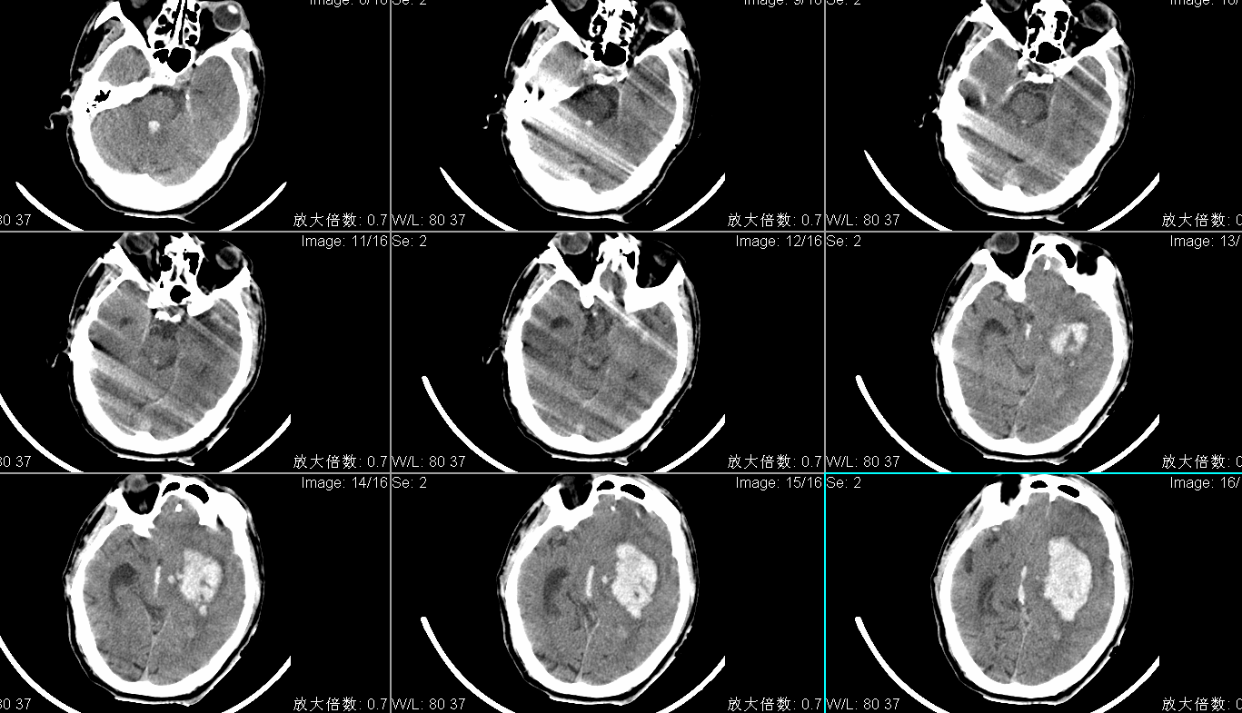

头CT显示左侧基底节区脑出血多田公式计算约100ml;